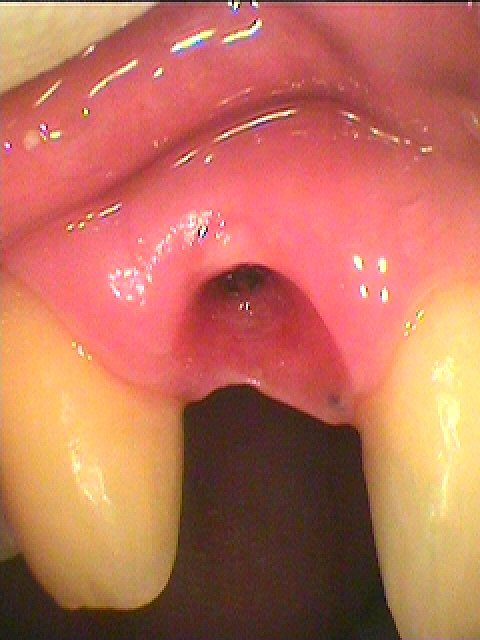

傷も落ち着きました

これよりプロビジョナルへ移行していきます